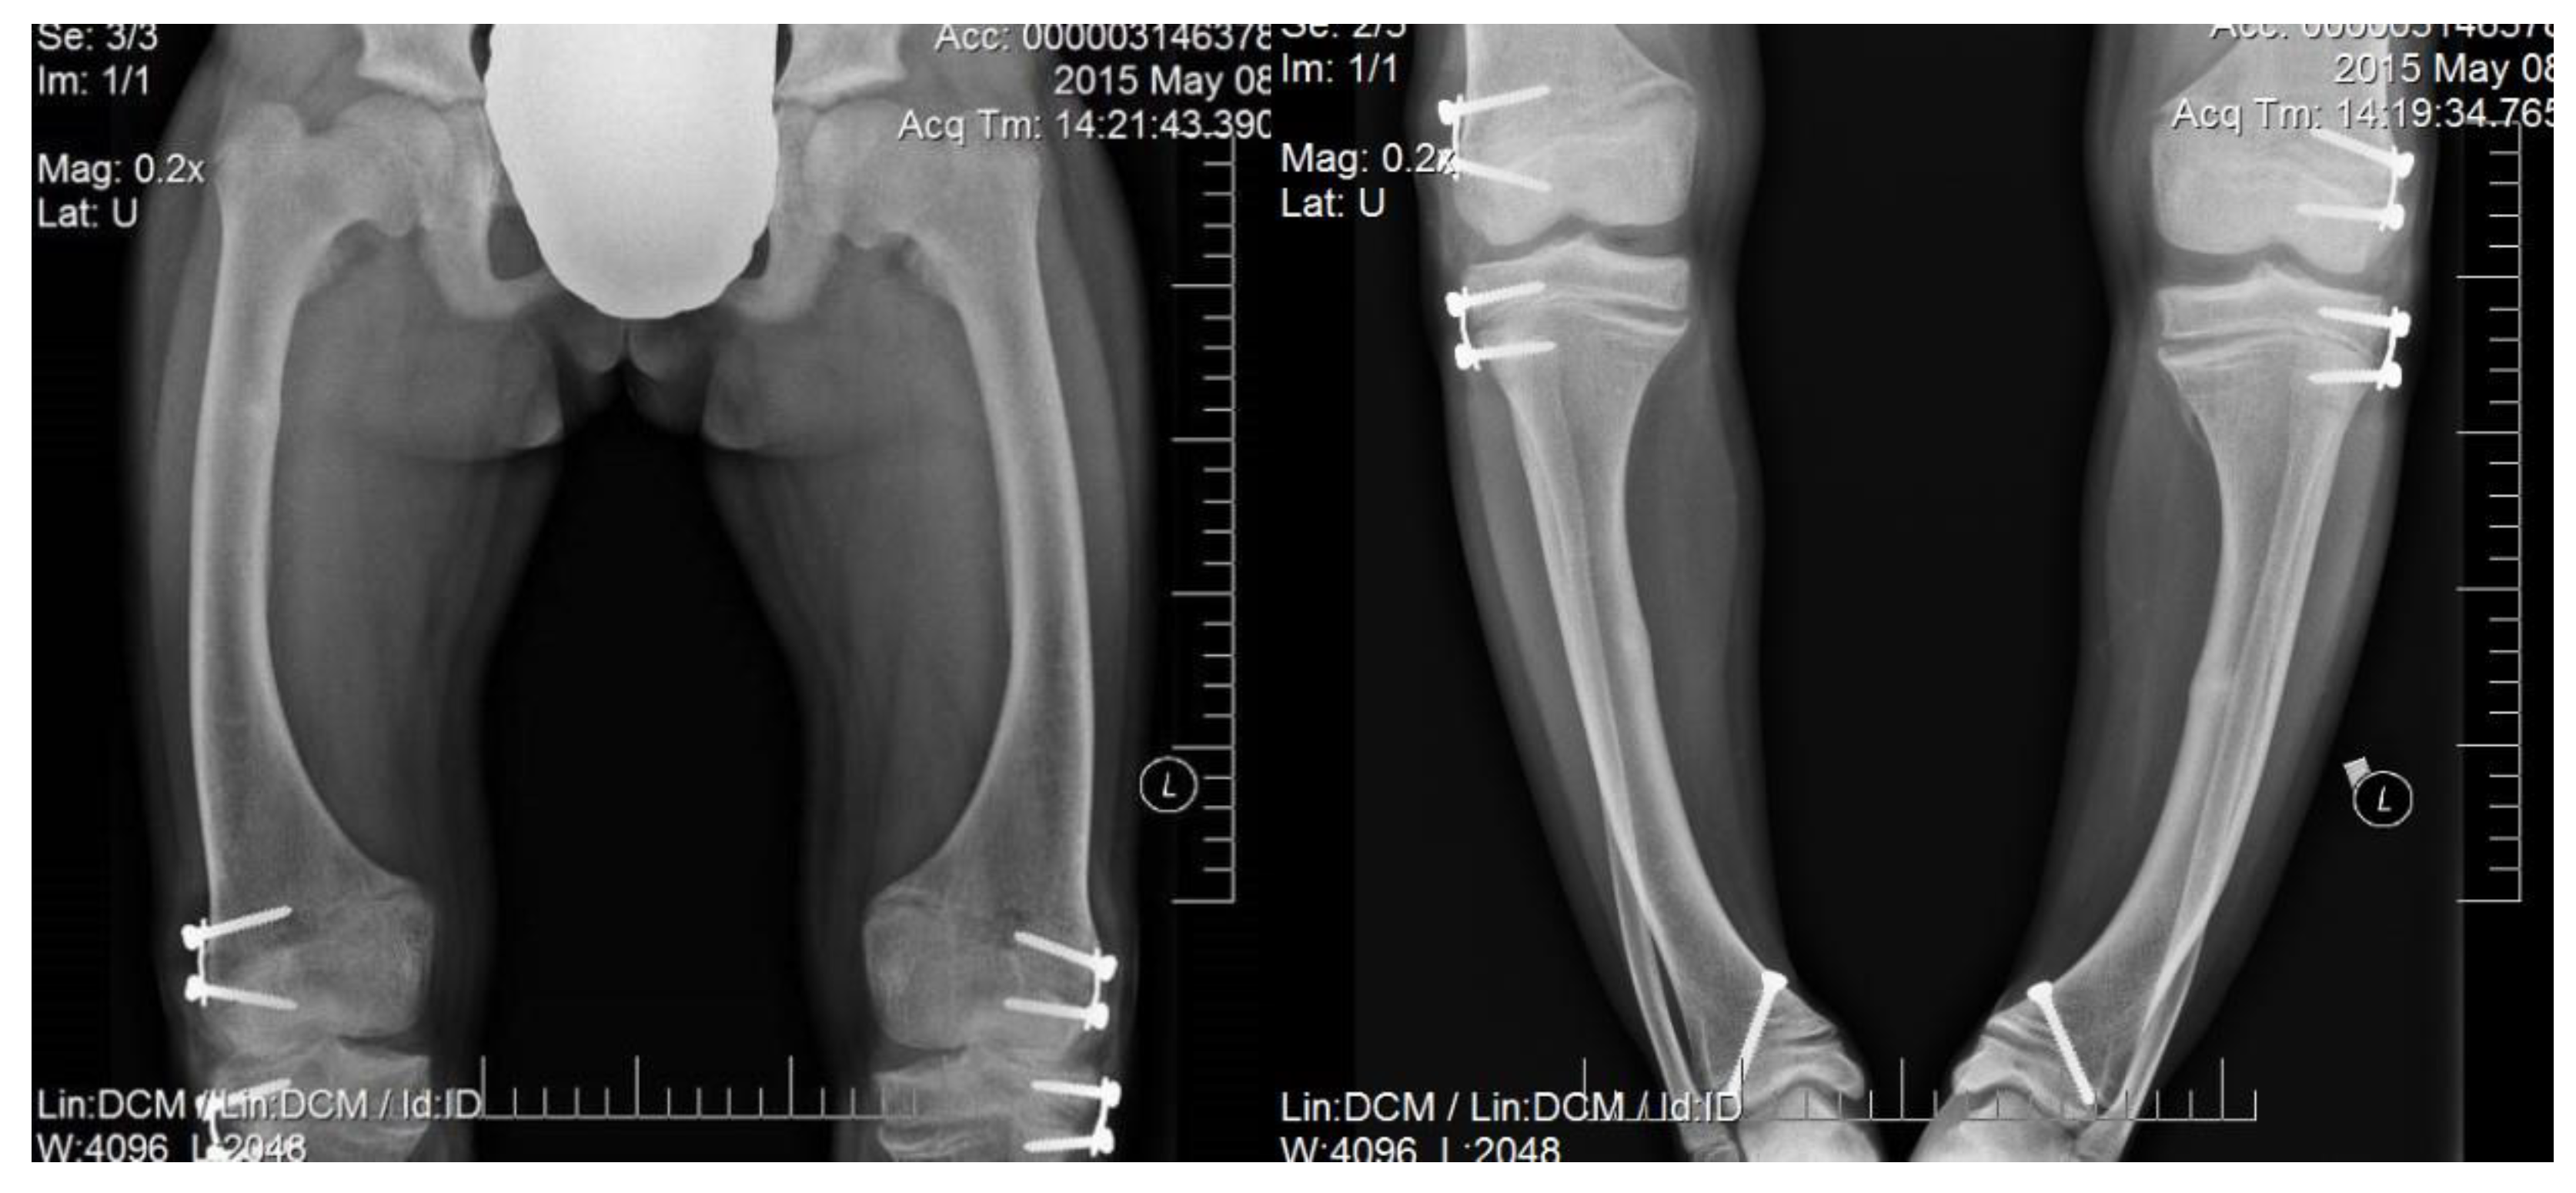

Irrespectively of inheritance pattern, all congenital forms of hypophosphatemic rickets present similar phenotypes including short height along with age and typical changes in the skeleton. Characteristic bone symptoms of hypophosphatemic rickets include varus deformity of the lower extremities, frequently severe, which appears after the child starts walking—usually in the 2nd year of life—that also progresses with age and may lead to gait disturbances and require surgical correction [6,7] (Figure 1 and Figure 2).

Figure 2.

A 5-year-old girl diagnosed with hypophosphatemic rickets; significant varus deformity of the lower extremities.